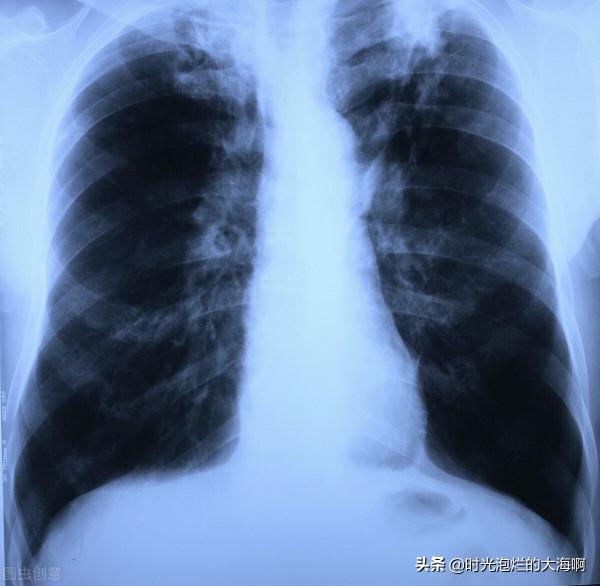

結核菌是一個抗酸桿菌(麻風菌也是抗酸菌),增殖緩慢。在人體中大致分為ABCD四群,(由於增生部位不同),在我國治療方法一般針對初發和復治兩種。前者是兩個月異煙肼、利福平和吡嗪醯胺,乙胺丁醇加上四個月異煙肼和利福平。當然由於實際情況不同,也可能多加一種藥物。5藥同用。 檢查時候當然以痰液中測得病菌最準確,若是沒有病菌可依據臨床症狀的明顯與否及胸片的表現決定治不治。(若痰液中沒有檢測到菌體,若是發熱乏力盜汗或是咳嗽咳痰咳血,二者之一合併胸片上斑片影或是大片實變影或是胸腔積液等一定要治療)。若是胸片上顯示結核球或是纖維空洞則不一定要治。當然要與肺癌影相區分,其一般周圍有毛刺徵和雲影。而且周圍分佈著較多病灶。結核球一般單發。